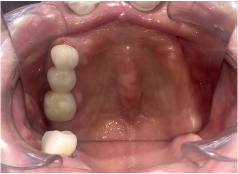

• Tình trạng răng trước đây:Mất răng toàn hàm, dùng hàm tháo lắp lâu năm bị tiêu xương hàm

• Bác sĩ chỉ định:Cấy ghép Implant toàn hàm All On 5

• Implant sử dụng:Implant Mis C1 Đức

• Răng sứ sử dụng:Răng sứ Titan Mỹ

• Cấy ghép Implant toàn hàm All On 5

• Phục hình răng sứ trên implant